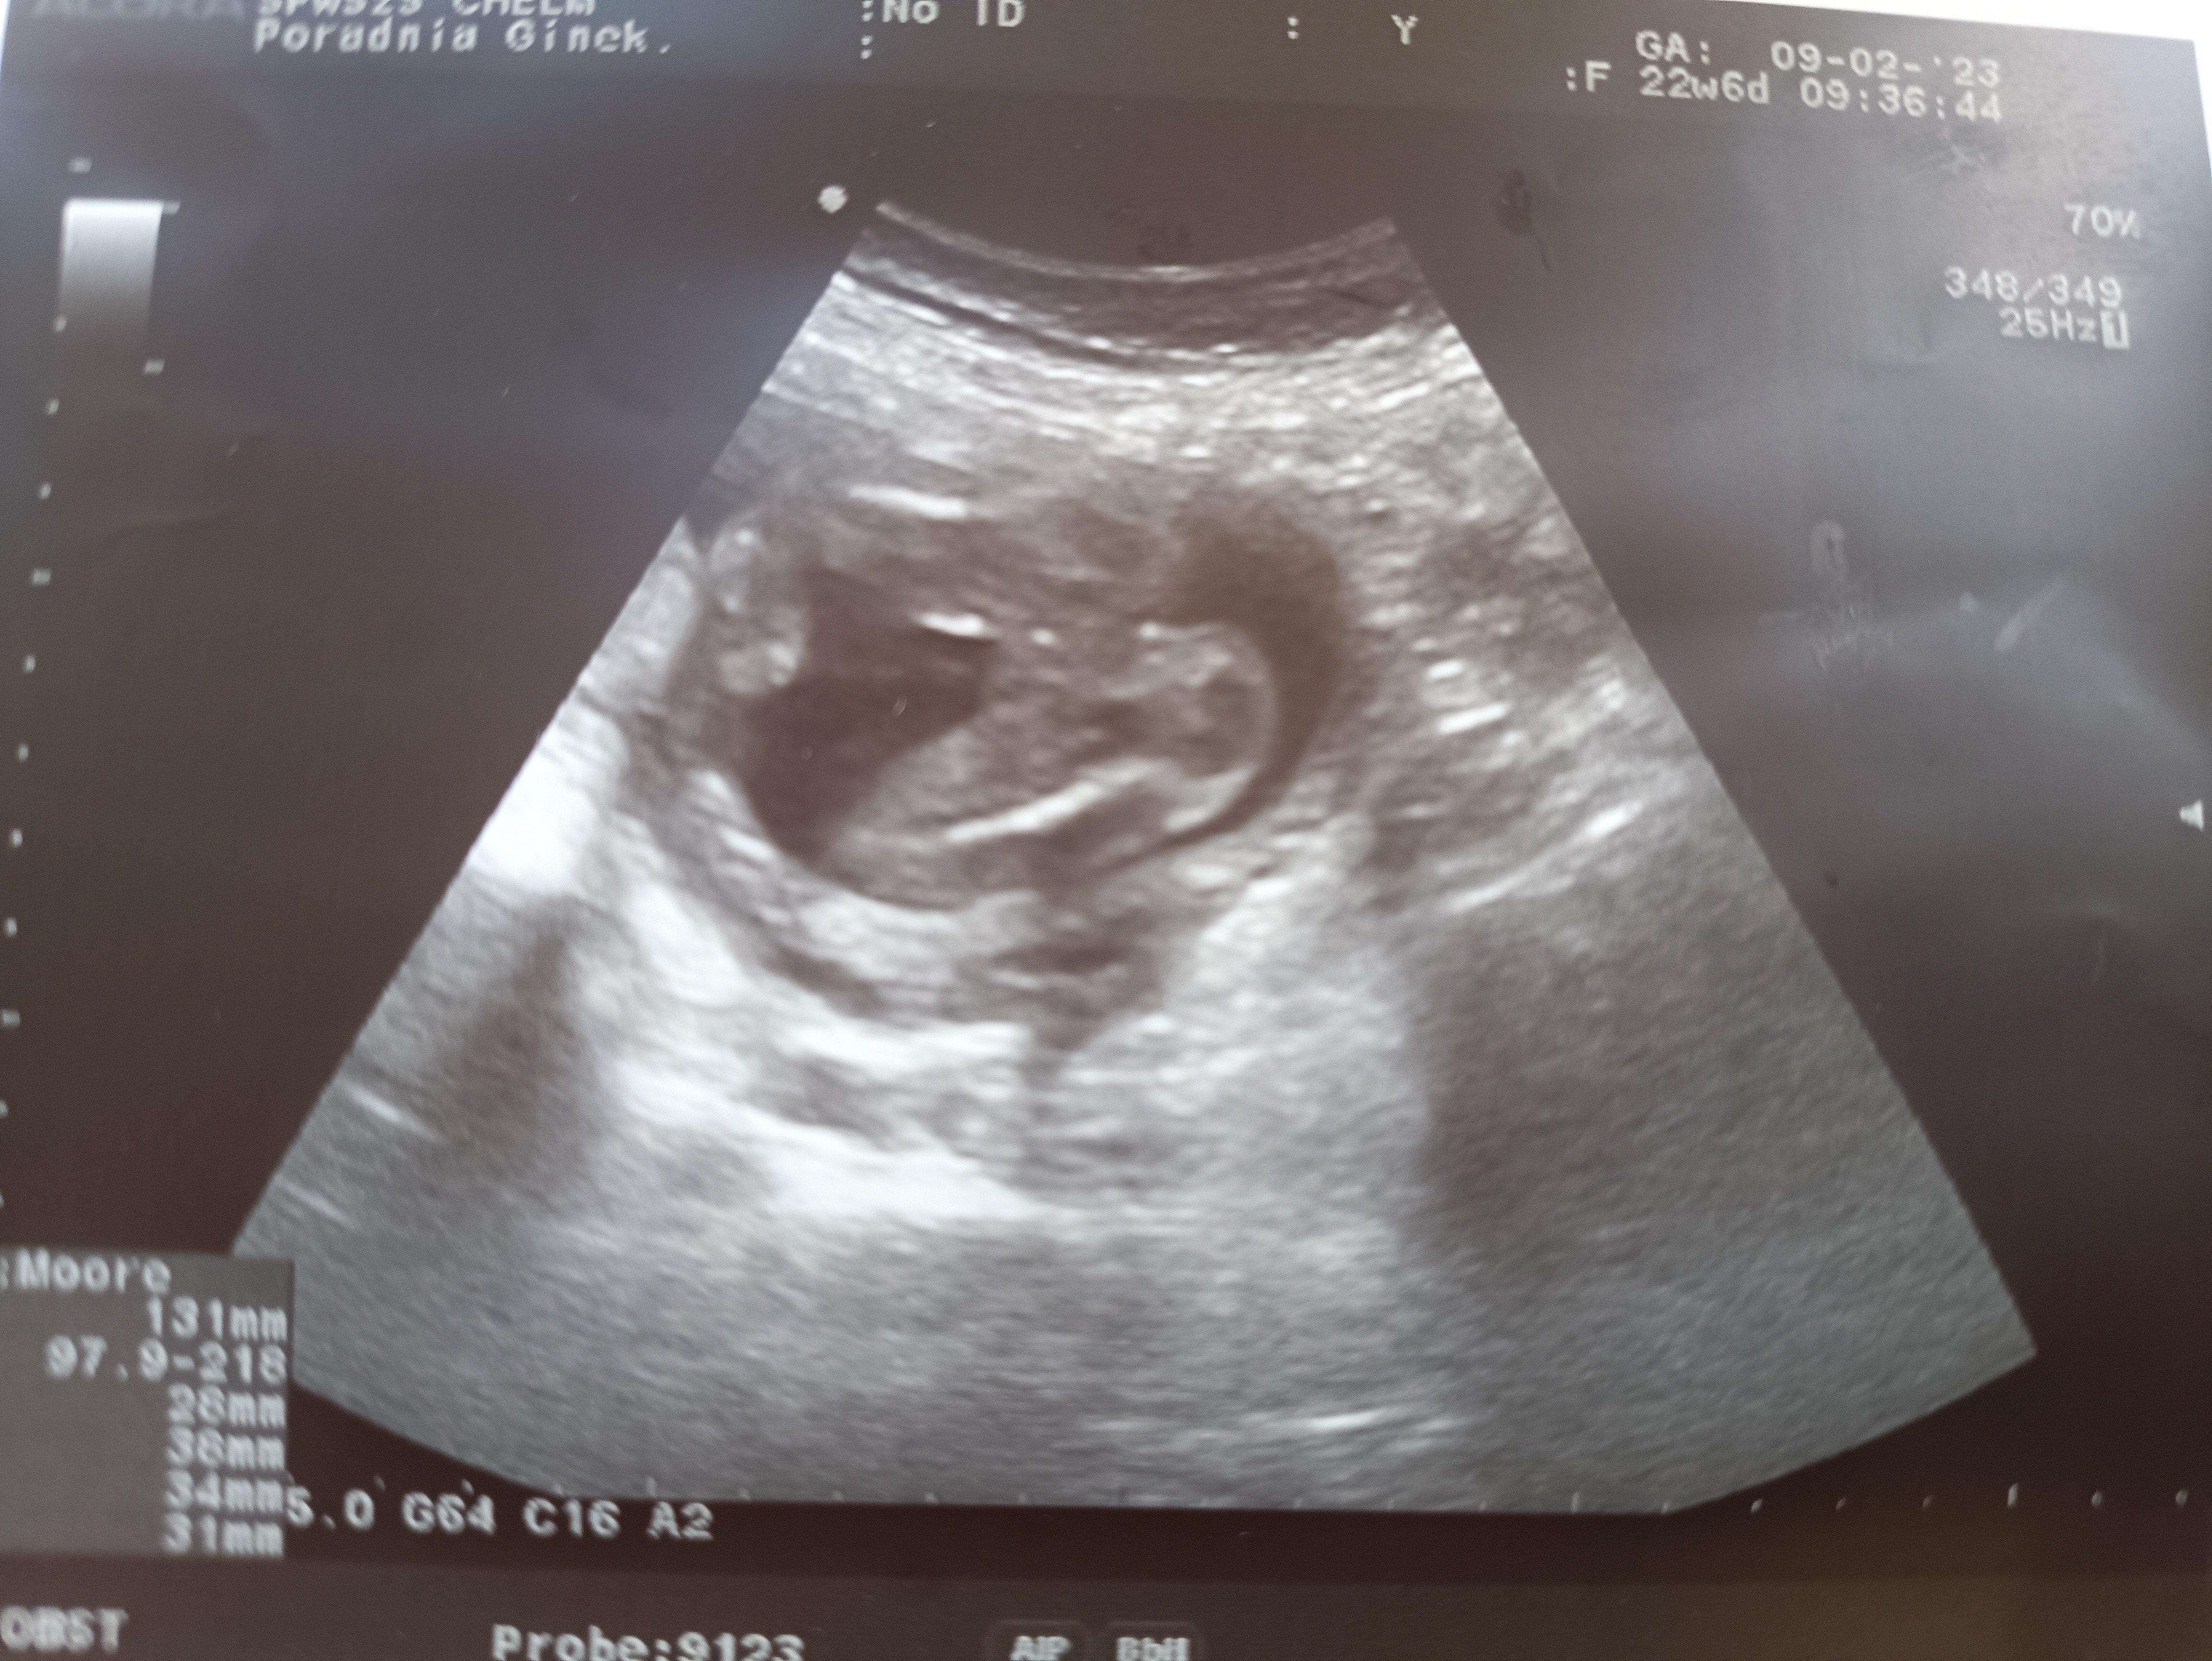

Dzisiaj (22+6) byłam na kolejnym USG i takie cuda wyszly 🙈 wcześniej była na 99% dziewczynka, dzisiaj już na 19 bo ten siurek pokazał się tylko na chwilę i zaraz zniknsl. Miał ktoś podobnie?

Chlopczyk :) u nas do 5 miesiąca każde badanie dziewczynka, później pokazał się siusiaczek i 3 prenatalne potwierdziły :) tu ewidentnie widać siusiaka, mieliśmy podobne zdjęcie:)